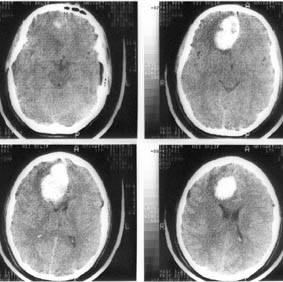

Компьютерная томография (КТ) и магнитно-резонансная томография (МРТ) — наиболее важные диагностические исследования при инсульте. КТ в большинстве случаев позволяет чётко отдифференцировать «свежее» кровоизлияние в мозг от других типов инсультов, МРТ предпочтительнее для выявления участков ишемии, оценки распространённости ишемического повреждения и пенумбры. Также с помощью этих исследований можно выявлять первичные и метастатические опухоли, абсцессы мозга и субдуральные гематомы. Если наблюдается ригидность затылочных мышц, но отсутствует отёк диска зрительного нерва, люмбальная пункция в большинстве случаев позволит быстро установить диагноз кровоизлияния в мозг, хотя при этом сохраняется незначительный риск возникновения синдрома «вклинения» мозга. В случаях, когда есть подозрения на эмболию, люмбальная пункция необходима, если предполагается применение антикоагулянтов. Люмбальная пункция имеет также важное значение для диагностики рассеянного склероза и, кроме того, может иметь диагностическое значение при нейроваскулярном сифилисе и абсцессе мозга[36]. При недоступности КТ или МРТ необходимо выполнить эхоэнцефалографию и люмбальную пункцию.